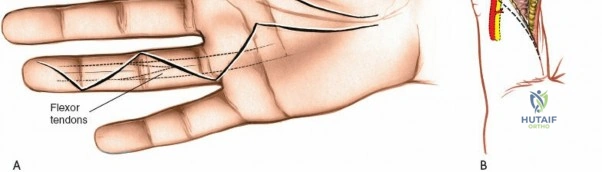

The skin incision must provide adequate exposure without creating straight lines across joint creases, which can lead to scar contracture. The Bruner zigzag incision is the standard for digital access due to its excellent exposure and prevention of flexion contractures. It incorporates the natural creases and extends proximally and distally in a zigzag fashion along the length of the digit. The apices of the V's are typically located over the mobile skin of the phalanges, avoiding the fixed skin over the joint creases.

- Finger Incision (Bruner): Begins dorsally/mid-laterally over the distal phalanx, angles volarly, crosses the volar skin crease, then angles back to the mid-lateral line, avoiding straight lines across joints. This allows creation of triangular skin flaps.

- Palmar Incision: Can be made as a curvilinear extension from the digital Bruner incision, often curving towards the thenar or hypothenar eminence, or as a transverse incision in line with the distal palmar crease. Incorporating a laceration directly into the incision is always preferred to minimize additional skin damage.

After marking the incision, the skin and subcutaneous tissues are carefully incised. In the digits, the triangular skin flaps created by the Bruner incision are elevated using fine skin hooks or small self-retaining retractors. Dissection should proceed in the subcutaneous plane, superficial to the digital neurovascular bundles, which run along the radial and ulnar borders of the digit, immediately adjacent to the flexor sheath.

Care must be taken to identify and protect these bundles. Any existing lacerations or hematomas are debrided. The digital nerves and vessels are carefully dissected free from the surrounding connective tissue and retracted, typically dorsally and laterally, using vessel loops or fine retractors to provide clear access to the underlying flexor sheath.

- Order of Repair: In the presence of both FDS and FDP injury, the FDP is typically repaired first, followed by the FDS. The FDS may be partially or completely excised if it significantly obstructs the FDP repair, but preservation is preferred.